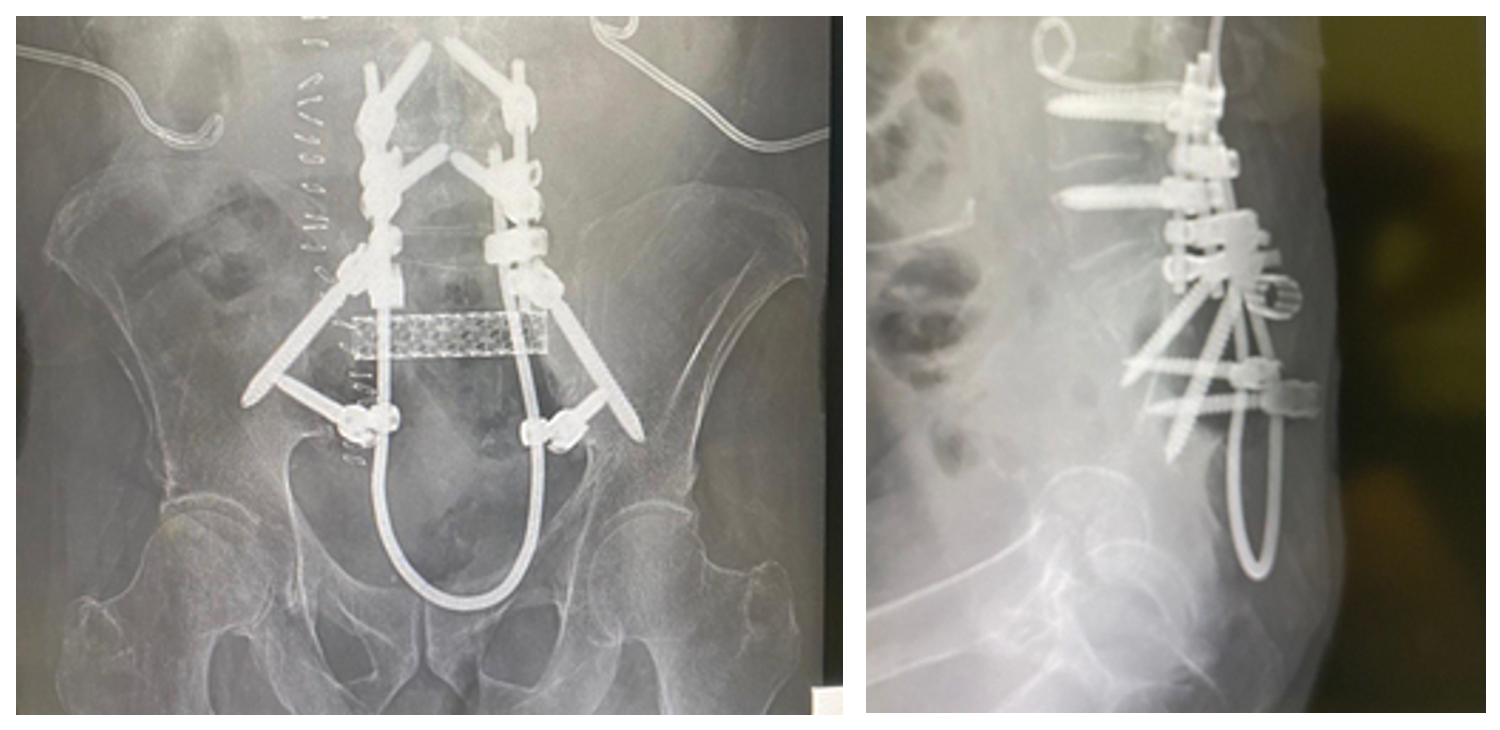

Ameliyat Sonrası: Röntgende total sakrektomi sonrası titanyum kafes ve lumbopelvik fiksasyon ile rekonstrüksiyon işlemi görülmekte.